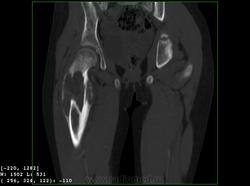

Девочка 9 лет. Родители отмечают, что 2 месяца назад девочка начала предъявлять жалобы на боли в правой пятке. Обследовались, патологии в стопе не нашли. Ребёнок постепенно начал хромать. А несколько дней назад обнаружили припухлость в в/3 бедра. Болей в бедре нет, как ночных, так и дневных. Температура не повышалась. Обратились за помощью - выполнены рентгенограммы, затем - КТ.

Злокачественная опухоль - виден луковичный периостит, инвазивный рост с лизисом кости. Но какая? Вроде бы растет из костного канала. Остеосаркома? Юинг? для этих опухолей структура какая-то больно хрящевая, мягкотканная. Хондросаркома? В таком возрасте? Почему нет клиники злокачественной опухоли кости, прежде всего - болей?

Коллеги, давайте правильно применять термины. Периостит - окончание воспаления, применяется при остеомиелите. При опухоли - периостоз - окончание избытка, продуктивного процесса. Здесь есть "козырек Кодмена", спикулообразный периостоз, но есть так же луковичный (слоистый) периостоз, который хорошо виден на отдельных КТ-срезах. Другое дело, что для диф. диагноза опухоли (то что процесс агрессивный - сомнений не вызывыает) это, по большому счету, ничего не дает. Однако, обратите внимание на вздутие. Считаю возможны варианты телеангиоэктатической или гигантоклеточной остеосаркомы. Так же не считаю возможным исключить саркому Юинга.

Да, рентгенкартина неоднозначна, конечно, в первую очередь надо исключать зло (Юинга, остеогенную), но не уверена на 100%, что это они, спикул нет, есть луковичный периостит ниже основного очага, но это не критерий злокачественности, вздутие. Был бы возраст помладше, в первую очередь подумала бы о гистиоцитозе или туберкулезе. Еще мысли об аневризмальной кисте и ГКО. Очень хочется узнать результаты гистологии.

+ Не потому ,что не согласен с остальными,просто не хочется девчонке "зла " ,а ,кстати на аксиальном срезе -горизонтальные уровни есть ,или это мне кажется ?-Если есть -тогда может быть и впрямь АКК?

Вы правы, коллега, мне тоже видятся уровни. Но если АКК, откуда периостоз? По КТ его оспорить сложно... По скиалогии, локализации наиболее подходит гигантоклеточная опухоль, тем более, что она часто сочетается с вторичной аневризмальной кистой. Но возраст?! хотя, чего сейчас только не бывает...